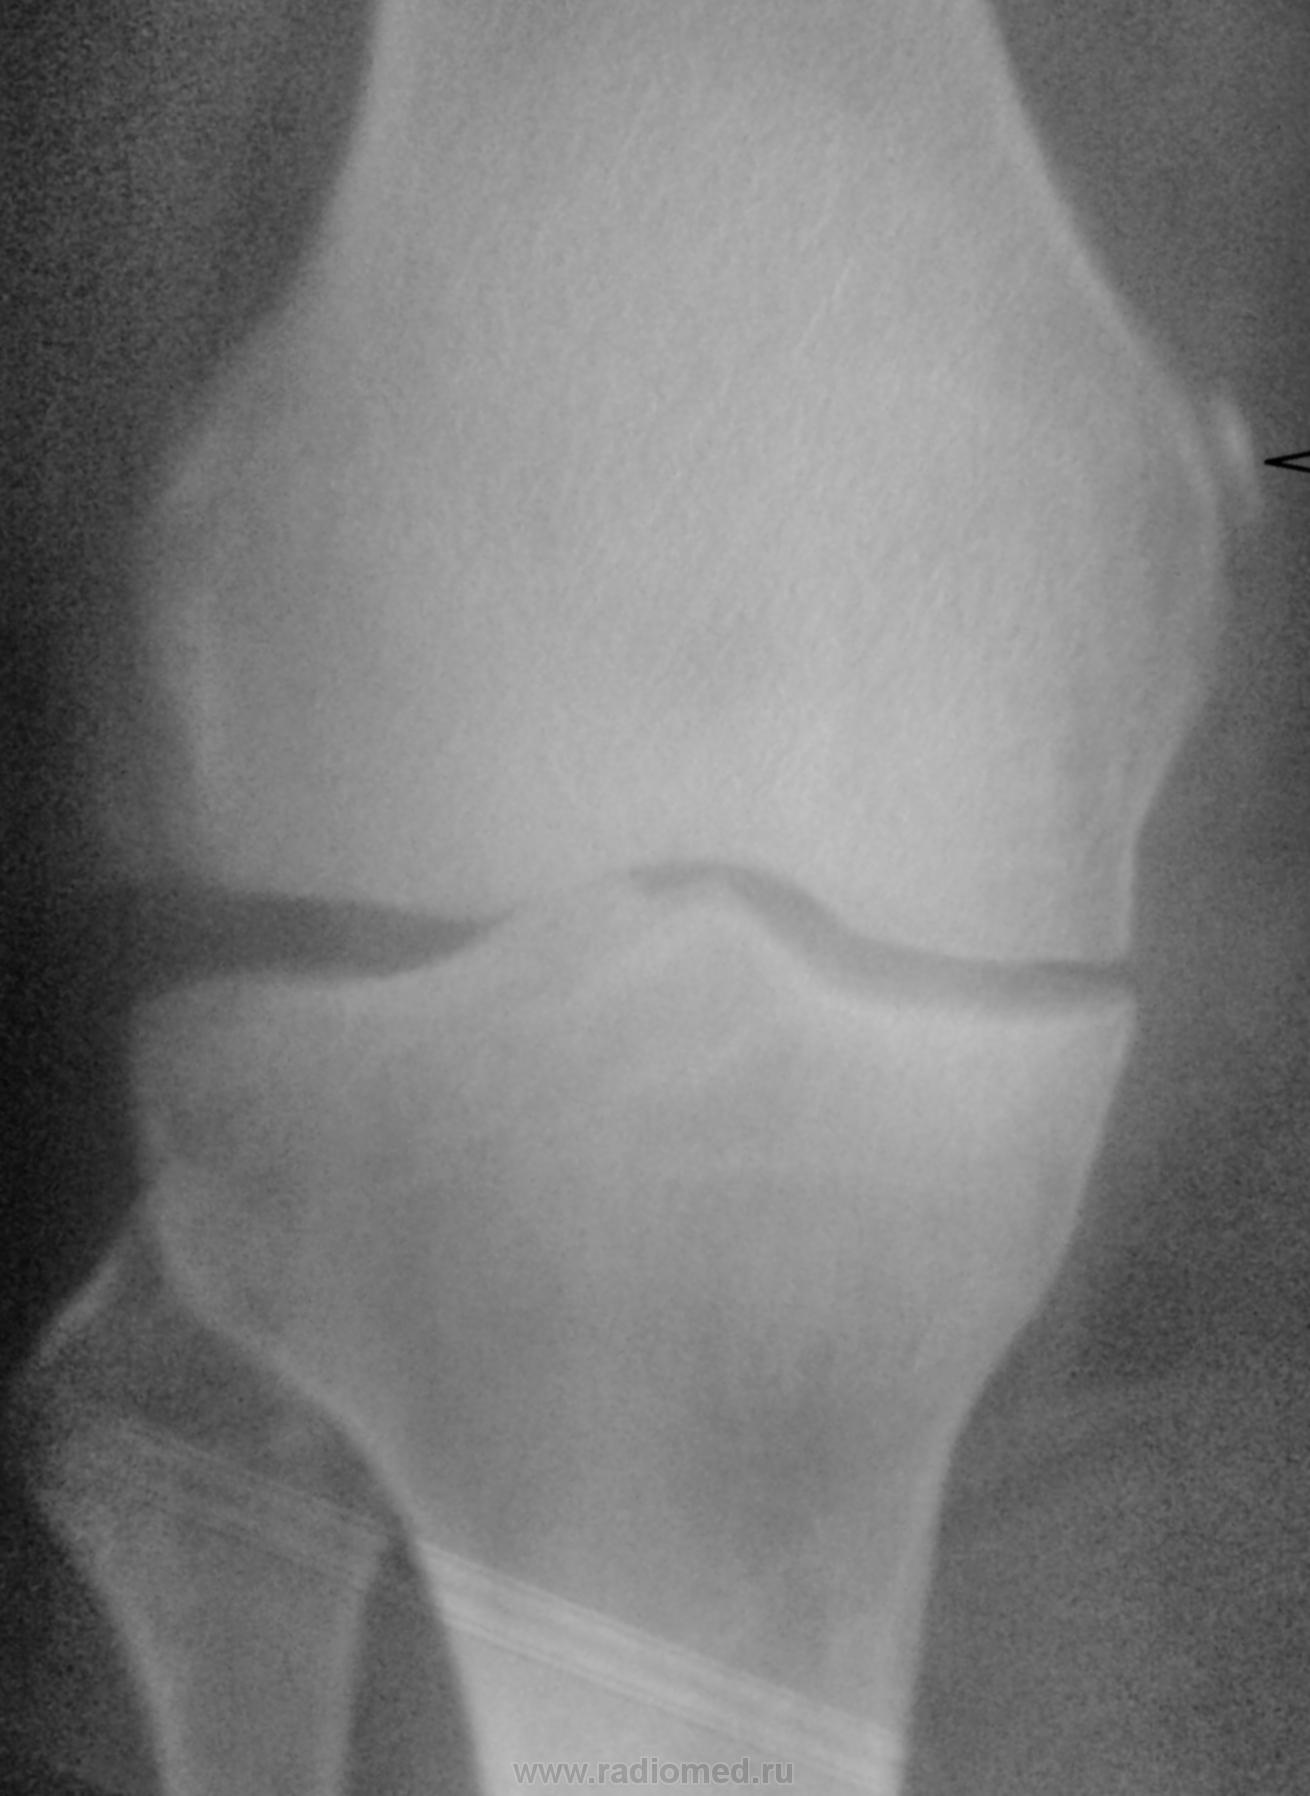

Пол пациента: Женский пол Тип патологии: Другое Область исследования: Скелетно-мышечная система Методы исследования: Rg Доброго времени суток! Коллеги, подскажите, что это может быть возле медиального надмыщелка бедренной кости? Пациентку 65 лет направил хирург с ДОА. Заранее спасибо. https://radiomed.ru/sites/default/files/styles/case_slider_image/public/user/12/12.foto0170-1.jpg?itok=EaLMu7dQ https://radiomed.ru/sites/default/files/styles/case_slider_image/public/user/12/13.foto0174.jpg?itok=p2Fa3XXR ID:24113 Пнд, 29/10/2012 - 23:01 #1 Almo Не на сайте Был на сайте: 9 часов 51 минут назад Зарегистрирован: 28.09.2008 - 18:50 Публикации: 8256 Тень Штида( внутренный мыщелок бедра). Пнд, 29/10/2012 - 23:02 #2 Андрей Юрьевич Не на сайте Был на сайте: 6 дней 14 часов назад Зарегистрирован: 16.11.2008 - 22:16 Публикации: 18098 Пеллегрини - Штиды болезнь http://www.radiomed.ru/publications/kss-pellegrini-shtida-bolezn Хотя в наше время считалось, что не болезнь это, а так, синдром. Андрей Юрьевич Пнд, 29/10/2012 - 23:05 #3 И.Бондаренко Не на сайте Был на сайте: 2 дня 7 часов назад Зарегистрирован: 13.09.2011 - 22:55 Публикации: 9206 +1 Втр, 30/10/2012 - 05:58 #4 Петр Николаевич Не на сайте Был на сайте: 3 года 10 месяцев назад Зарегистрирован: 15.03.2011 - 13:22 Публикации: 150 Болезнь Пеллегрини - Штида +1 Втр, 30/10/2012 - 19:31 #5 maker4ik Не на сайте Был на сайте: 8 лет 7 месяцев назад Зарегистрирован: 19.10.2011 - 17:49 Публикации: 2682 Плюсую к Пеллегрини-Штида.

Тень Штида( внутренный мыщелок бедра).

Пеллегрини - Штиды болезнь http://www.radiomed.ru/publications/kss-pellegrini-shtida-bolezn Хотя в наше время считалось, что не болезнь это, а так, синдром.